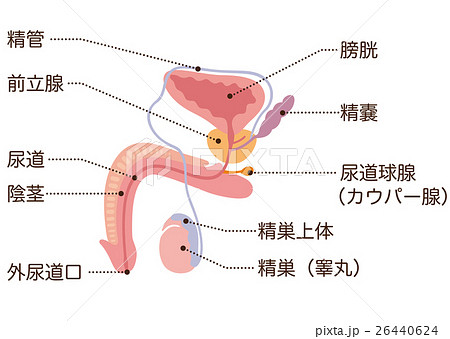

男性生殖器断面人体図 名称付き メディカルイラスト図鑑 無料の医療 美容素材集

男性生殖器断面人体図 名称付き メディカルイラスト図鑑 無料の医療 美容素材集

男性生殖器 断面図 Stock Illustration Adobe Stock